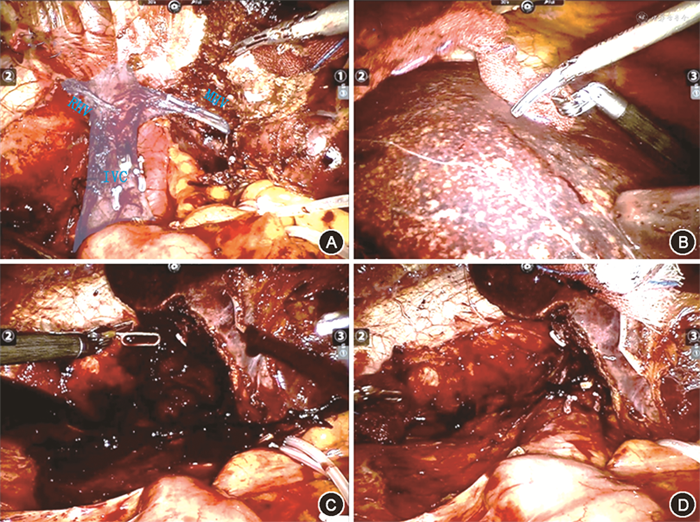

1. 半肝切除术:半肝入肝血流阻断+选择性Pringle法。首先切除侧半肝入肝管道鞘内解剖、离断,切除过程中,根据断肝路线选择性辅以保留侧半肝阻断(此时,可以直接采用Pringle法),减少左右肝交汇带(Cross Interface)内的出血。

S5+8肝脏切除术,肝外鞘内或肝实质内(联合Pringle法)鞘外解剖右前肝蒂、离断,离断左侧肝脏断面时阻断左侧半肝入肝血流,此时肝脏右后区域的血供未阻断,离断右侧肝脏断面时阻断右侧半肝入肝血流,此时肝脏左侧半肝区域的血供未阻断,左右侧交替阻断,交替控制S5+8段两侧交汇带内的血液,整个切肝过程中,肝脏血流并未完全阻断,以减少肝脏缺血性损伤。

S4+5+8中肝切除术,肝外或肝实质内解剖右前肝蒂并离断,左侧沿左侧叶间裂离断肝脏时,阻断左侧半肝入肝血流,此时肝脏右后区域的血供未阻断,右侧肝脏离断时阻断右侧半肝入肝血流,此时肝脏左外叶区域的血供未阻断。左右侧交替,术中注意保护左右侧肝静脉主干及左右保留侧肝蒂。

先肝外(无需Pringle法)或肝实质内(联合Pringle法)解剖肝段/肝叶的肝蒂并离断,完成解剖性入肝血流阻断;其次根据肝段所在位置和断肝界面,选择适宜的半肝血流阻断。例如S6+7(右后区)肝脏切除,可以先解剖和离断右后肝蒂,断肝过程中联合右侧半肝血流阻断,用以控制S6+7左侧离断面处交汇带血流,整个切肝过程,左侧半肝的血流未阻断,用以减少肝脏缺血性损伤。

另有几点应注意:(1)术中所有半肝阻断不好实施时都可以改为Pringle法;(2)微创下Pringle和半肝血流全腹腔内阻断方法:微创下2/3长度的8号导尿管双次环绕收紧肝十二指肠韧带,借助Hem-o-lock夹固定,术中短暂放开肝门阻断可以使用超声刀离断Hem-o-lock夹,收紧后再夹闭可以实现再次肝门阻断;(3)保留侧半肝血流阻断时一般无需鞘内解剖,简单分离肝十二指肠韧带浆膜后直接采用血管阻断夹夹闭阻断侧肝门即可,如切除侧肝门已离断,Pringle法等同对侧肝门阻断。